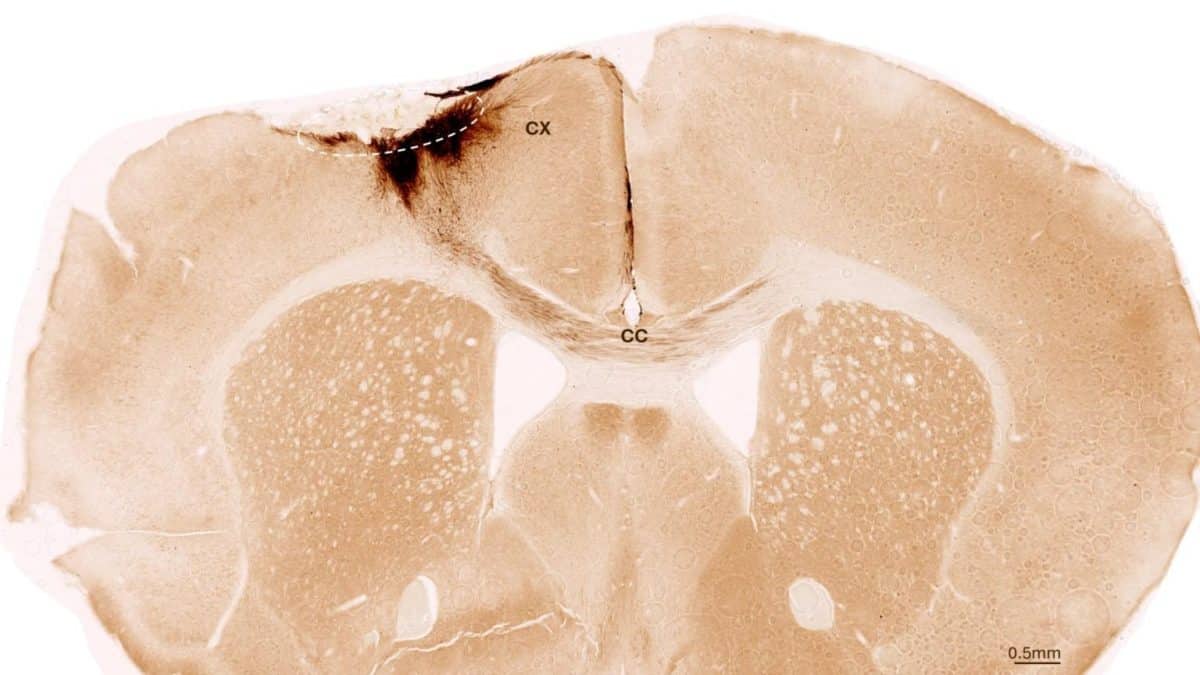

Исследователи вызвали у мышей перманентный инсульт, характеристики которого близки проявлению инсульта у человека. Животных генетически модифицировали, чтобы они не отторгали стволовые клетки человека.

Через неделю ученые трансплантировали стволовые клетки в поврежденную область мозга. Они следили за результатами, используя различные визуализирующие и биохимические методы. Исследователи обнаружили, что стволовые клетки выживали в течение всего периода наблюдения — пяти недель. Большинство из них превратились в нейроны, взаимодействующие с уже существующими клетками мозга.

Исследователи обнаружили и другие признаки регенерации: образовывались новые кровеносные сосуды, уменьшались воспалительные процессы и улучшалась целостность гематоэнцефалического барьера. Трансплантация стволовых клеток у мышей также обратила двигательные нарушения, вызванные инсультом.